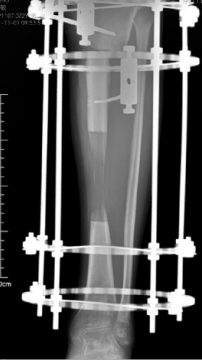

多年来,贵州航天医院各科室紧跟医学前沿,不断强技术、补短板,大力开展新技术、新项目,完成了许多高精尖、高难度、本地区“首例”的技术,填补了医院医疗技术空白,满足了群众日益增长的医疗需求。 贵州航天医院骨科率先在遵义地区开展骨搬移技术,截至目前,已治愈慢性骨髓炎、感染性骨不连、骨缺损、脉管炎、糖尿病足患者200余例,糖尿病足治疗保肢率达到98%。 本期,我们将为大家带来骨科特色技术——骨搬移技术(Ilizarov)。 案例分享 一名59岁的患者,身患糖尿病12年,在来我院3个月前出现了右脚溃烂的症状,来院就诊时,患者的右脚十分红肿,右脚脚趾坏死,伤口处不断流出黑红色脓液,情况十分严重。在接诊到患者时,骨科专家团队高度重视,立刻为患者完善了CT血管造影(CTA)等相关检查,诊断为:2型糖尿病,糖尿病周围血管病变,右糖尿病足。 术 前 考虑到患者情况比较严重,为最大限度保证患者肢体完整,科室专家团队进行了严格的讨论评估,为患者制定了骨搬移技术治疗方案,在征得患者及其家属的同意后,成功通过搬移骨块为患者进行治疗,促进患者病变肢体血管再生。 胫骨横向骨搬移外架固定 清除感染病灶 术后调节外架,通过搬移骨块 促进患肢血管再生 患者在术后三周前来换药,观察到感染得到进一步控制;术后六周复查,患者病变处已愈合,进行CT血管造影(CTA)后可明显观察到足部血管再生。 术后3周 术后6周愈合 CT血管造影见足部血管再生 糖尿病患者全身与局部的问题互为影响,形成恶性循环,糖尿病足溃疡创面迁延不愈,常见干性坏疽、湿性坏疽、趾坏死、深且大的溃疡以及骨髓炎等症状,还可导致脓毒血症,以往为保全生命,患者被迫选择一次或多次截肢。骨搬移技术的发展进步,能在血糖有效控制、局部有效清创下,有效促进患肢微血管再生,改善患肢血供,达到糖尿病足更快治疗康复的目的,并能根据病变情况最大限度的保障患者肢体完整。 什么是骨搬移技术 骨搬移技术是通过使用专用的骨外固定器固定骨段,每天缓慢牵拉,在牵拉搬移过程中,骨段尾部形成新骨及新的软组织,从而修复骨骼缺损及软组织缺损。是治疗大段骨缺损、骨不连、骨感染、肢体畸形的金标准方法,也用于治疗脉管炎、糖尿病足等肢体缺血性疾病。 骨感染缺损 切除感染段 搬移骨段 新骨形成 骨感染根治愈合 骨搬移技术原理 生物组织在持续、稳定、缓慢牵拉下,能刺激细胞分裂、组织再生,骨外固定技术运用该原理,通过持续缓慢调节外固定器形成牵拉张力,促进牵引成骨与相邻组织再生,如神经、血管、肌肉、皮肤等再生,达到治疗大段骨缺损、肢体缺血如糖尿病足等疾病的目的。 骨搬移技术优势 (一)除治疗骨缺损、骨不连外,有更广的适用范围,利用组织再生、血管再生等特性,能大量运用于肢体畸形的矫形、糖尿病足等的治疗。 (二)治疗效果确切,重建肢体外型和功能,极大降低截肢率和残疾率。 (三)明显提高了患者生活质量,极大减轻其家庭及社会负担。 肢体畸形的矫形 慢性骨髓炎 骨段切除 术后1年 濒临截肢的脉管炎术后6周 难愈创面术后3周 贵州航天医院骨科 专家团队 赵学平 骨科主任 主任医师 临床擅长:从事骨科临床工作30余年,对骨科常见疾病的诊治具有丰富的临床经验。 世界中医药联合会脊柱康复专业委员会常务理事,中华中医药学会整脊分会常务委员,中国中西医结合学会骨伤科分会肢体矫形功能重建与康复专家委员会常务委员,中国研究性医院学会骨科创新与转换专业委员会关节外科学组保髋工作委员会常委,中国康复技术转化及发展促进会骨外科与康复技术转化专业委员会常务委员,泛珠三角区域运动医学联盟(PPRD-SMA)理事会常务理事,中国研究型医院学会运动医学专业委员会委员,贵州省中医药学会整脊分会副主任委员,贵州省中西医结合学会银质针专业委员会副主任委员,贵州省康复医学会骨与关节专业委员会常务委员,贵州省人民医院骨科专科联盟常务理事,贵州省康复医学会骨内科专业委员会常务委员,中华医学会贵州省骨科学会委员,贵州省康复医学会脊柱脊髓专业委员会常务委员,贵州省运动医学分会委员,贵州省康复医学会骨与软组织肿瘤专业委员会委员,遵义市医学会创伤分会副主任委员,贵州省康复医学会骨内科专业委员会遵义地区分会常务委员,遵义市医疗事故鉴定、伤残鉴定、工伤鉴定、司法鉴定专家。 长期从事骨科临床研究及教学工作,在国家级、省部级杂志发表论文20余篇,SCI论文2篇,参与主编骨科专著2部,主持省部级科研项目2项,参与指导省部级、市级科研项目6项。 陈明勇 骨科副主任 副主任医师 临床擅长:从事创伤骨科工作约20年,对骨缺损、骨不连、骨肿瘤、肢体畸形等的肢体矫形重建及功能重建,慢性化脓性骨髓炎的根治治疗、糖尿病足的保肢治疗、快速康复理念(ERAS)下的老年骨折的诊治,四肢复杂骨折的诊治,四肢骨折等微创手术治疗具有丰富的临床经验。 2004年毕业于遵义医学院临床专业,曾在中国人民解放军总医院、广西医科大学第一附属医院、上海第六人民医院骨科进修。中国中西医结合学会骨伤科专业委员会横向骨搬移治疗糖尿病足及微血管网再生学组首届委员,遵义市医学会创伤分会常务委员。 瞿 辉 骨科 副主任医师 临床擅长:对骨科的常见病、关节外科、脊柱外科及运动医学疾病的诊治具有丰富的临床经验,熟练掌握骨科手术操作技术。 毕业于遵义医学院临床医学系,2005年前往广州中山大学第一附院骨显微医学部进修学习,2011年前往成都华西医院进修学习,并多次在省内外学习骨科相关知识,是中华医学会骨科分会会员。 赵兴东 骨科 主任医师 临床擅长:擅长骨科的常见病及各种创伤、四肢骨折创伤修复、骨感染、手足疾病的诊治和手足体表畸形的矫形整复,熟练掌握骨科四肢骨病及创伤的手术操作技术,尤其在四肢关节复杂性损伤、手足外伤、组织缺损创面、难治创面的皮瓣修复方面及平足、高弓足矫形方面及四肢慢性疼痛诊治、康复方面具有丰富的临床经验。 硕士研究生,毕业于遵义医学院临床外科系,2015年前往山东省立医院手足外科进修学习;遵义市医学分会创伤分会第一、二届委员,遵义市手外科医学会第二委届员会常务委员;在省级及省级以上期刊发表文章9篇,参编著作2部,参与主持并完成市级课题1项,参与市级课题2项、省级课题1项。 张俊凯 骨科 副主任医师 临床擅长:从事骨科临床工作28年,对创伤骨折、骨感染、骨缺损、骨不连等外科诊治,四肢骨折的微创手术治疗,四肢复杂骨折(如关节内粉碎性骨折、多发骨折等)的损伤控制及手术治疗等具有丰富的临床经验。 1995年毕业于遵义医学院临床专业,2009年前往复旦大学附属医院骨科进修1年。 卢懿明 骨科 副主任医师 临床擅长:从事骨科工作18年,对创伤骨折、四肢骨折的微创手术治疗、四肢复杂骨折(如关节内粉碎性骨折、多发骨折等)的损伤控制及手术治疗,尤其是髋部骨折的PFNA等微创技术,踝关节骨折、膝关节周围骨折的Mipo微创技术等具有丰富的临床经验,开展了4项新技术,发明6项新型专利技术。 2005年毕业于遵义医学院临床专业,2017年,前往南方医科大学第三附属医院骨科进修半年,回院后运用Mipo技术对骨干骨折及干骺端骨折的治疗技术,同时积极开展骨盆骨折、髋臼骨折腹直肌外侧切口的应用;发表了多篇专业论文,经常参与省内外学术交流会授课,获得医院荣誉称号多个。 邬夏荣 骨科 副主任医师 临床擅长:从事骨科工作16年,对四肢复杂骨折、骨肿瘤的诊治,尤其是足踝创伤、慢性踝关节损伤、平足症等诊疗具有丰富的临床经验。 2006年毕业于遵义医科大学临床医学专业,曾在陆军军医大学西南医院进修学习,发表多篇骨科学术论文。 余德怀 骨科 副主任医师 临床擅长:从事骨科工作10余年,对运动医学、骨关节、脊柱外科常见病、多发病的诊治具有丰富的临床经验。 硕士研究生,2011年毕业于遵义医学院临床医学专业,曾前往遵义医科大学附属医院运动医学专业进修学习;是贵州省医学会运动医学分会青年委员,西部关节镜联盟委员;发表多篇骨科学术论文。 冯 乾 骨科 副主任医师 临床擅长:从事骨科工作近20年,熟练掌握骨科多发病及常见病的诊治,尤其对脊柱退变性疾病的诊断及治疗具有丰富的临床经验,主要研究脊柱微创相关治疗方式,能熟练开展椎间孔镜及VBE。 曾前往北京大学第三医院进修学习疼痛及椎间孔镜、首都医科大学友谊医院专业进修脊柱内镜;是贵州省康复医学会第三届脊柱脊髓专业委员会委员;发明专利3项、发表脊柱外科专业论文多篇。 张艳金 骨科 副主任医师 临床擅长:从事骨外科工作16年,对复合伤、多发伤的救治、四肢骨干骨折、关节周围骨折、骨肿瘤、骨髓炎等诊治具有丰富的临床经验。 中共党员,硕士研究生,2006年本科毕业于山西医科大学第二临床医学院,2011年研究生毕业于北京军区总医院;在“老年COPD患者合并髋部骨折的诊治”国际合作课题组研究两年,在老年髋部骨折的诊治方面具有丰富的经验,并发表论文6篇;承担遵义市级课题1项;承担遵义医科大学的临床教学工作,获得遵义医科大学优秀带教老师荣誉。编撰有《骨科疾病诊疗精粹》一书,开展2项新技术,编撰地方规范《务川自治县创伤骨科常见疾病诊疗规范》一书。 赵小锋 骨科 副主任医师 临床擅长:从事骨科临床工作11年,对骨科常见病、多发病诊疗有较为丰富的临床经验,擅长脊柱相关疾病诊断及治疗,尤其是颈、腰、腿疼痛疾病诊断及治疗,擅长胸腰椎骨折微创经皮穿刺内固定术、经皮穿刺椎体成形术、经皮穿刺脊柱内镜下腰椎间盘摘除术、单纯开创腰椎间盘摘除术、腰椎滑脱复位椎间植骨椎融合内固定术、腰椎管狭窄减压融合内固定术及人工髋、膝关节置换术等。 2012年毕业于遵义医学院外科学专业硕士研究生,2019年参加“遵义市115医学人才精英计划”于上海交通大学第一附属医院培训学习,2023年于北京大学第三人民医院脊柱外科进修学习,曾获得遵义市优秀医师荣誉称号。 遵义市手外科第一届委员,遵义市医学会创伤分会第一届委员,遵义市医学会创伤分会第二届委员,贵州省康复医学会第三届脊柱脊髓专业会委员,遵义市医学会烧伤与整形外科学分会委员,发表论文5篇,其中国家级核心期刊1篇,SCI论文1篇,主持市级课题1项并结题,参与市级课题2项。 贵州航天医院骨科简介 基本情况 贵州航天医院(原3417医院)骨科组建于1968年,前身是以创伤和断肢(断指)再植闻名于世的上海市第六人民医院骨科,中国断肢(断指)再植的奠基者、中科院院士陈仲伟等著名专家、学者多次莅临科室指导医疗、教,是贵州省最早拥有专业骨科技术科室之一,在70年代开展了贵州省首例断肢(断指)再植手术。组建50余年来,诊治患者已逾百万,挽救了无数的伤病员,成为了保障遵义地区人民群众健康的重要支撑。 经过几代人的不懈努力,今天的骨科,已由创伤骨科发展至骨病、骨肿瘤、骨结核等领域,现有脊柱外科、关节外科、四肢创伤、手足外科四个亚专科,成为了集医疗、教学、科研于一体的综合学科,是贵州省临床重点专科、遵义市临床重点专科、遵义市骨科临床医学中心、遵义市基层骨科专科联盟理事长单位。 科室目前开放床位110张,共有医护人员50余人,副高级以上专家18人,硕士研究生15人。拥有一流骨科医疗设备多台,每年不定期选派优秀技术骨干到全国各大知名医学院校进修、学习、参观、交流,并邀请国内、国外知名专家教授来院进行交流、指导,通过不断引进国内外先进的诊疗技术,科室医疗技术水平稳步提升,为广大人民群众提供了优质的医疗服务。 专科特色 骨一科 (一)骨缺损、骨不连的肢体与功能重建 胫骨横向骨搬移技术治疗糖尿病足: (二)慢性骨髓炎的根治治疗 (三)肢体缺血性疾病如糖尿病足、脉管炎的保肢治疗 (四)皮瓣修复 (五)复杂创伤的治疗 (六)老年髋部骨折及小儿骨折快速手术 老年髋部骨折: 骨二科 (一)胸腰椎骨折微创经皮椎弓根螺钉固定术 (二)老年性骨质疏松性患者腰椎滑脱脊柱内固定术(骨水泥螺钉) (三)V形双通道脊柱内镜技术(VBE)腰椎融合术治疗腰椎退行性疾病 (四)老年性骨质疏松性骨折(PVP/PKP)术 (五)人工髋关节置换术 (六)双侧股骨头坏死人工全髋关节置换 (七)右侧全髋置换术后假体周围骨折翻修 (八)人工膝关节置换术 (九)人工膝关节假体松动翻修 (十)关节镜技术 传统手术切口 关节镜技术切口 诊疗范围 骨一科 1.四肢创伤、矫形。 2.手、足踝外科。 骨二科